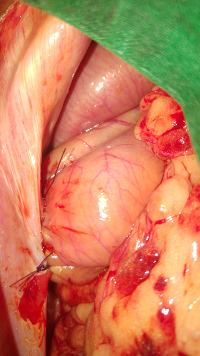

-rupture du ligament croisé (prothèse ligamentaire)